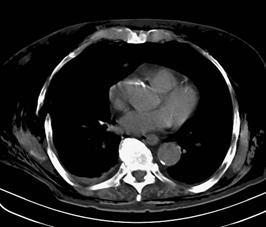

Corp ascutit penetrat in regiunea precordiala Mediastin largit

Aortograma Mediastin largit

Leziune la nivelul istmului aortic

Aortograma.Leziune

situata distal de Aorta

clampata

emergenta arterei subclavii stangi Segment

lezat excizat